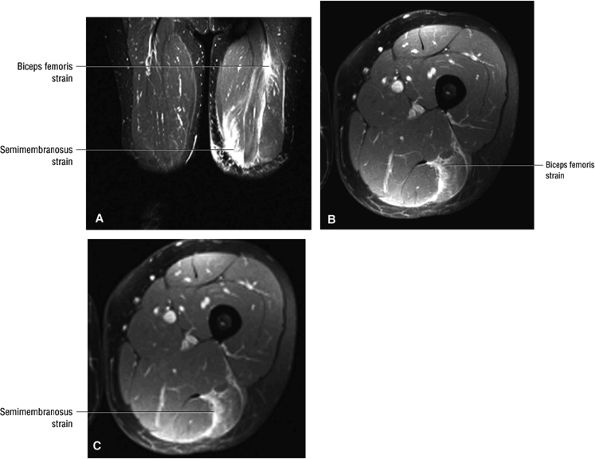

FIGURE 3.25 ● BICEPS FEMORIS The biceps femoris extends the thigh and flexes the leg in external rotation of the tibia, contributing to lateral stability of the knee. The muscles of the hamstring group (biceps femoris, semimembranosus, and semitendinosus), except for the short head of the biceps femoris, all cross the hip and the knee joint. Musculotendinous junctions extend the entire length of the muscle and serve as potential sites for strains. The short head is innervated by the peroneal branch of the sciatic nerve; the other hamstring muscles derive innervation from the tibial branch of the sciatic nerve.

|

![]() |

FIGURE 3.26 ● SEMIMEMBRANOSUS The semimembranosus extends the thigh and flexes the leg. It is part of the hamstring muscle group (biceps femoris, semimembranosus, and semitendinosus) in the posterior thigh. Except for the short head of the biceps, the origins of the hamstring tendons are from the ischial tuberosity and are involved in ischial avulsion fractures in the young athlete.